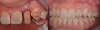

Figure 14 through Figure 18 show a partially dentate patient for whom a fully digital workflow was utilized. This 47-year-old male presented with root blunting and mobility of teeth Nos. 7, 8, and 9 (Figure 14). A thermoplastic clip was attached during the CBCT, and an intraoral scan was taken and superimposed on the CBCT. The case was then planned in the navigation planning software (Figure 15). Once the teeth were extracted, intraoral scanning was performed. The intraoral scan was imported into lab software (Figure 16), and a PMMA milled screw-retained prosthesis was fabricated. The prosthesis was placed the next morning (Figure 17). Two months later, a new intraoral scan was taken to capture the mature soft tissue, and the final milled titanium abutment and restoration were delivered (Figure 18).

Fig 14. Preoperative view of a partially dentate case. Patient with root blunting and grade 3 mobility.

Figure 14

Fig 15. The case was planned using navigation planning software in this same patient.

Figure 15

Fig 16. Virtual design of the provisional prosthesis.

Figure 16

Fig 17. Views of the milled PMMA screw-retained provisional restoration. Note the screw access holes in the incisor edges (left panel). (Images courtesy of Dr. Kim Knoll.)

Figure 17

Fig 18. Placement of the final prosthesis. Milled titanium abutments (left panel) and Emax crowns (right panel). (Images courtesy of Dr. Kim Knoll.)

Figure 18